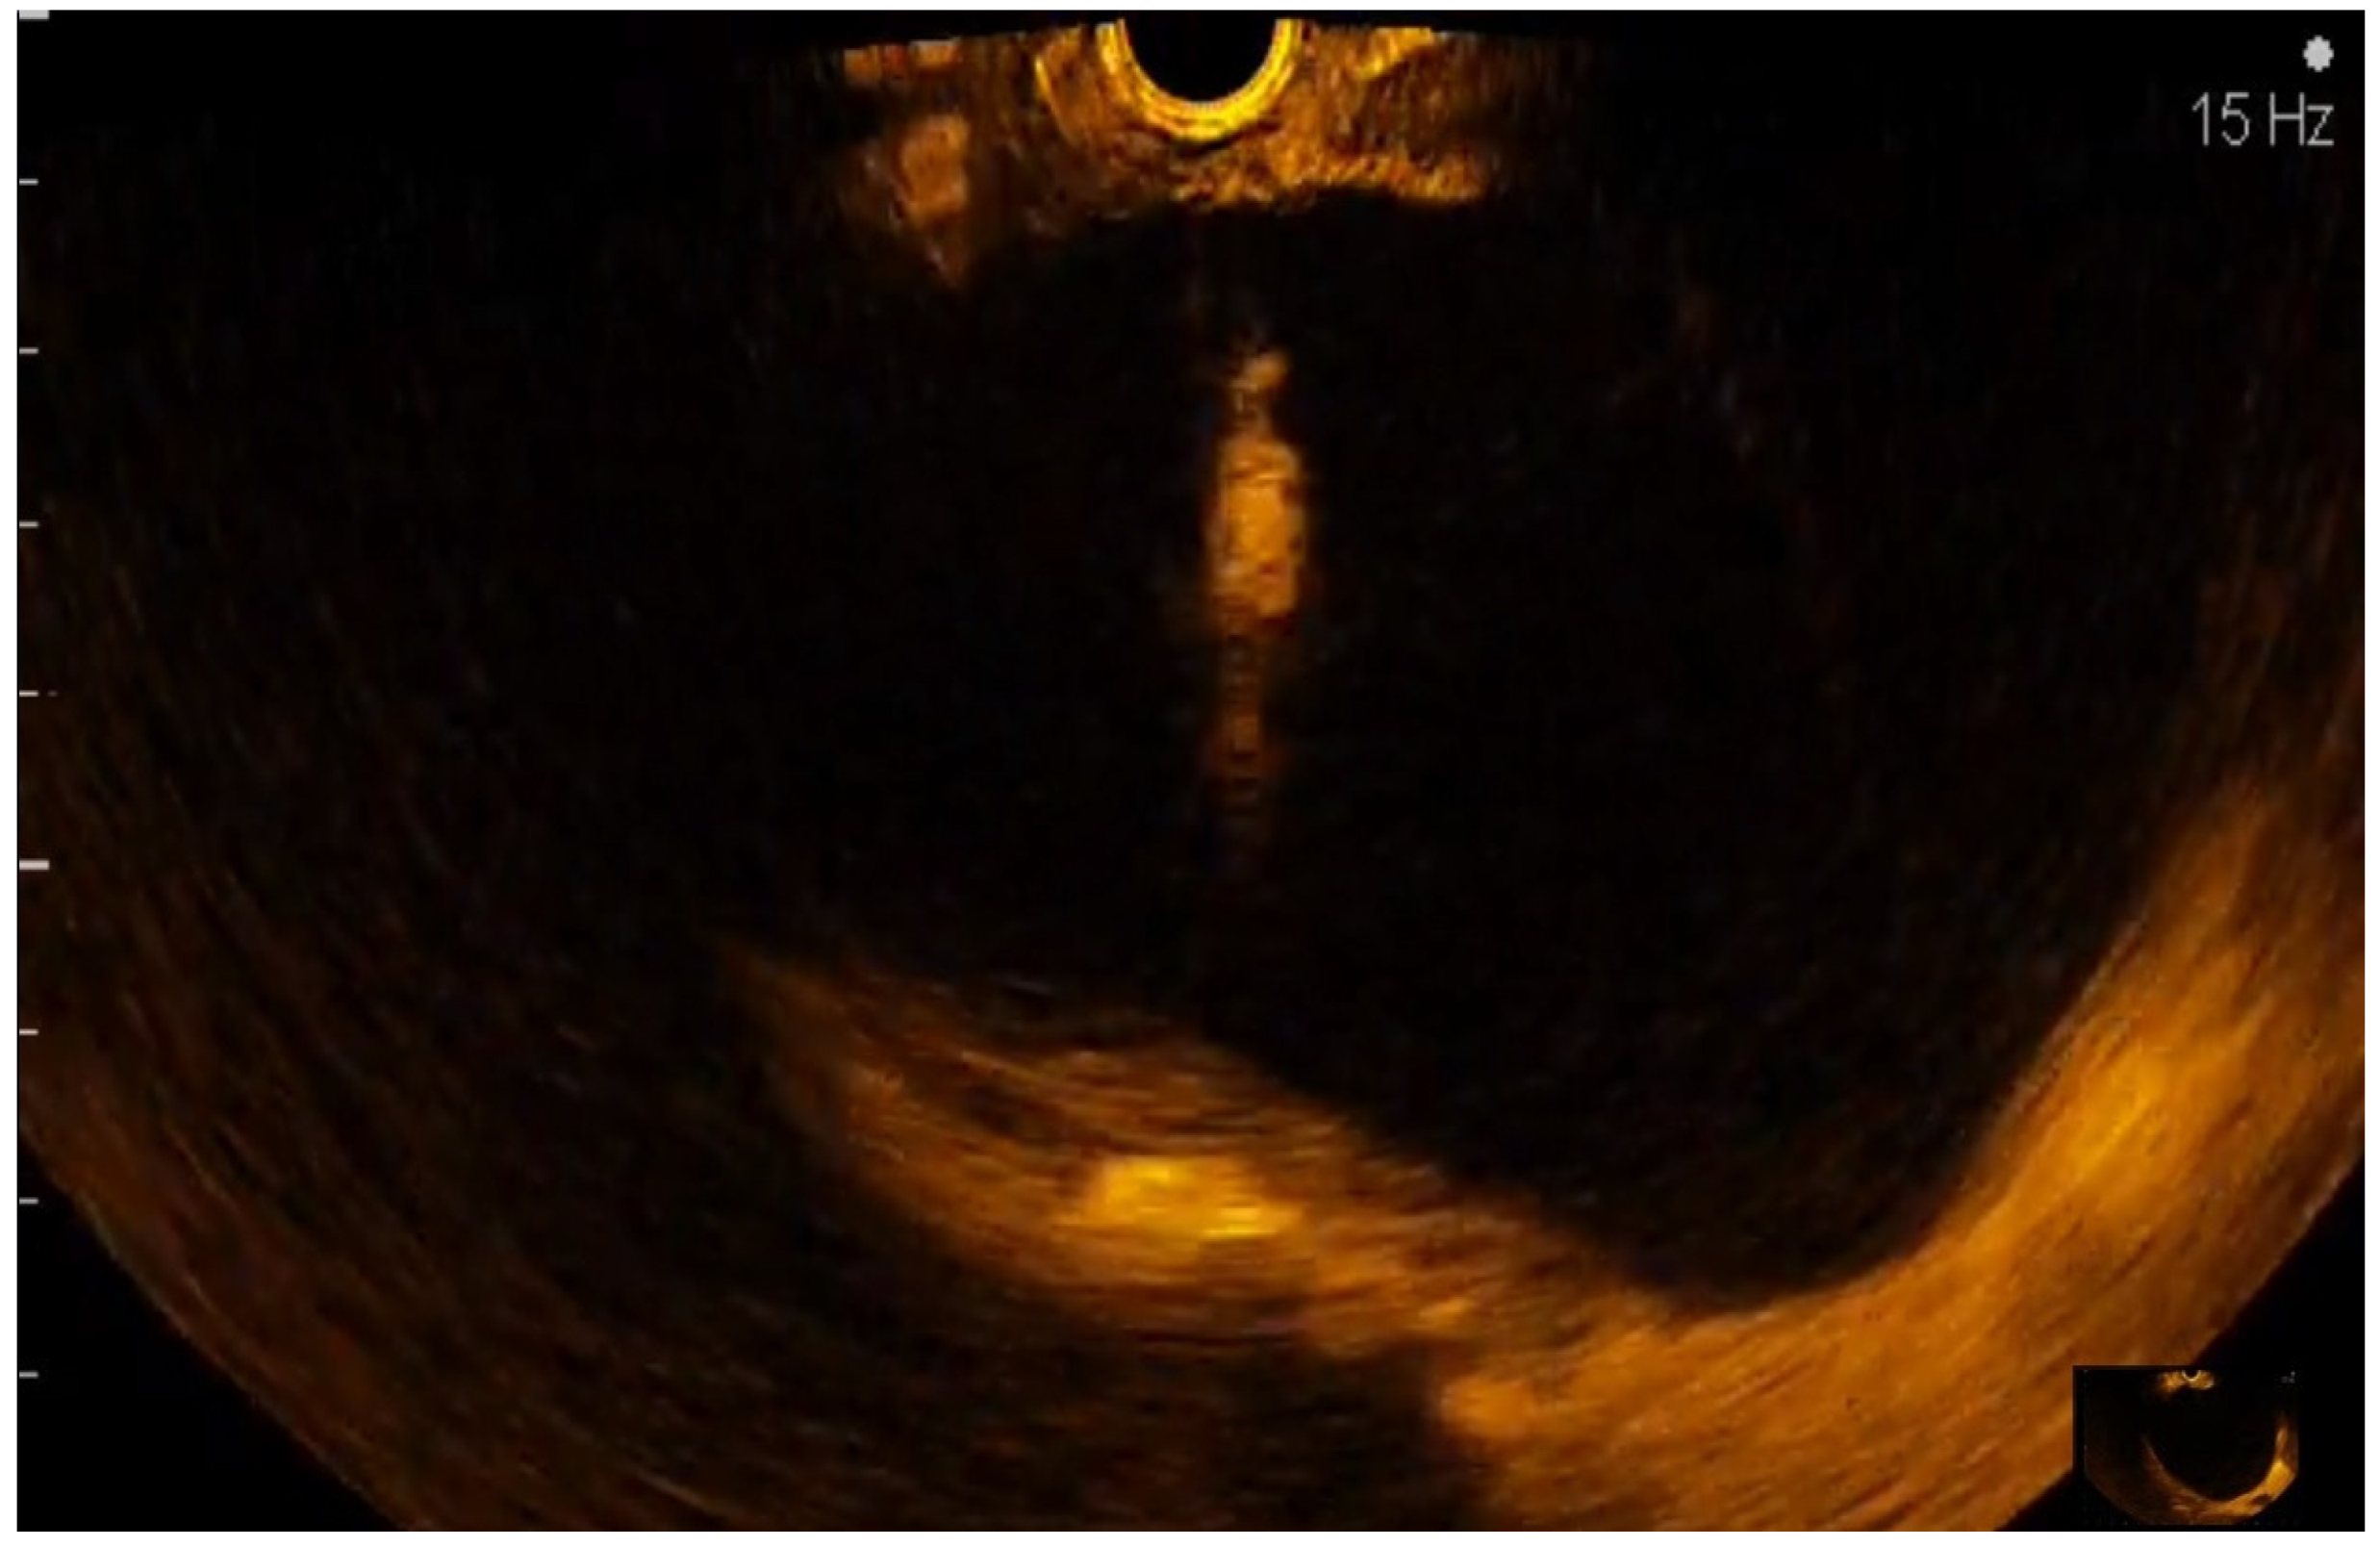

2.5. CE-EUS Procedure

- the contribution of associating CE-EUS with EUS-FNB for differentiating solid pancreatic lesions without on-site cytopathology

3.2. EUS-FNA/FNB + CE-EUS of Solid Pancreatic Lesions Subgroup